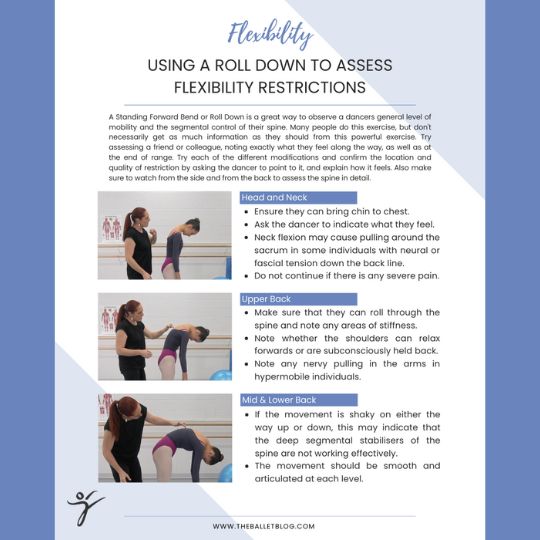

Another position I see young students trying to achieve in order to get more flexible is oversplits in second position. Unfortunately stretching young hips past their natural physiological range runs the risk of permanent damage, so we need to be very careful in how we achieve mobility in this position. Any flexibility training requires an intelligent and multifactorial approach, with a deep understanding of human anatomy guiding its application. Doing this ensures that young dancers will be able to continue dancing well into adulthood and live a normal, pain free life when they do decide to stop performing.

Just to clarify - I have no issues with extreme mobility when achieved safely, and with the appropriate control. In fact, much of the work I do with the high level, elite students is focused exactly on this. However we focus on achieving this through educated and intelligent, up to date, smart ways, to avoid any potential issues, and the students are educated to manage their own bodies. This means that they will be able to continue dancing well into adulthood, and be able to live a normal, pain free life when they do decide to stop performing.

Anyone training young students, and the parents of these students need to be very aware of the possible dangers when trying to improve mobility. The students themselves often find it difficult to see the long term consequences of their actions, and for them, achieving a certain position is often their end goal. It is our responsibility to learn the safest possible ways to help them to achieve their goals, as well as educating them on the appropriateness of their goals to their chosen career.